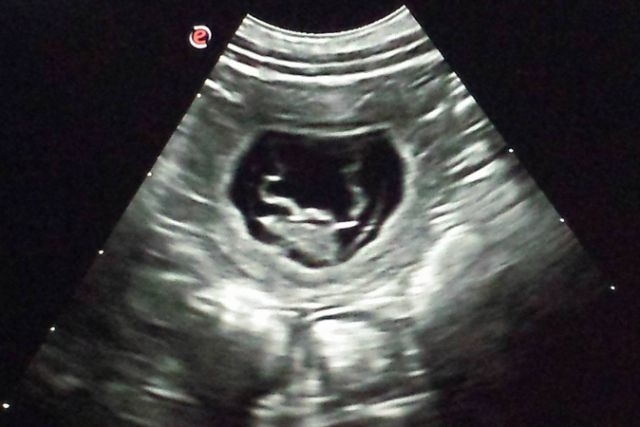

17.02.2017 8. Trächtigkeitswoche – Hedlund wird runder 🙂